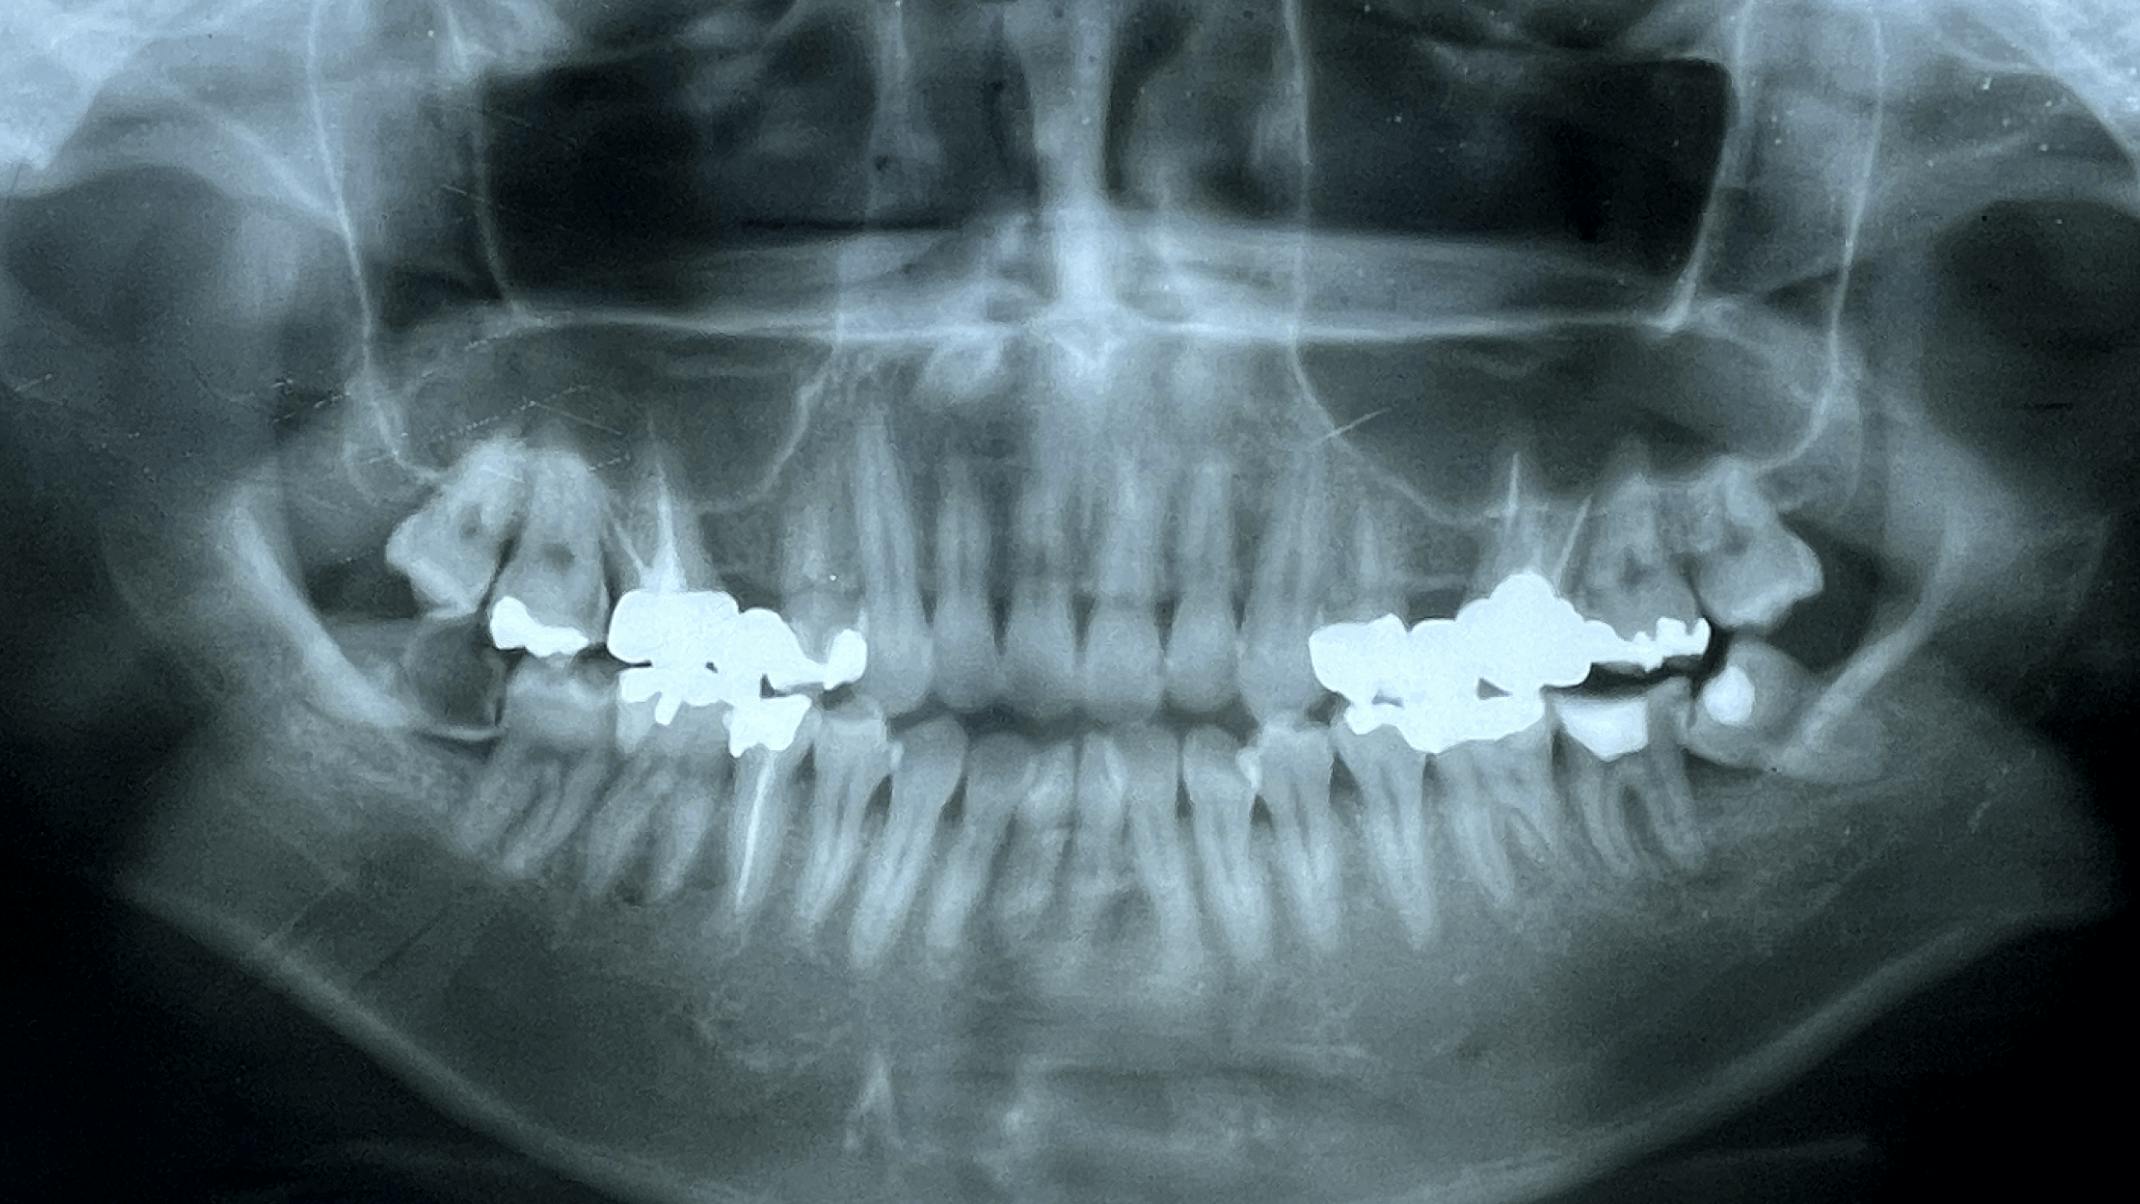

Root Canal Treatment精密根管治療

根管とは、神経や血管などが通っている歯の根の内部のこと。

根管は細くて形状も複雑なため、

歯科医療の中でも特に専門性と精度の高さが求められる分野です。

根管が感染を起こしてしまっている場合は、感染した箇所や汚れを同時にきれいにする「感染根管治療」を行います。むし歯の進行の程度によっては、抜髄(歯の神経を取る処置)を行うこともあります。

当院では最新の機器と技術により、患者様にご安心いただける精密な処置を行います。